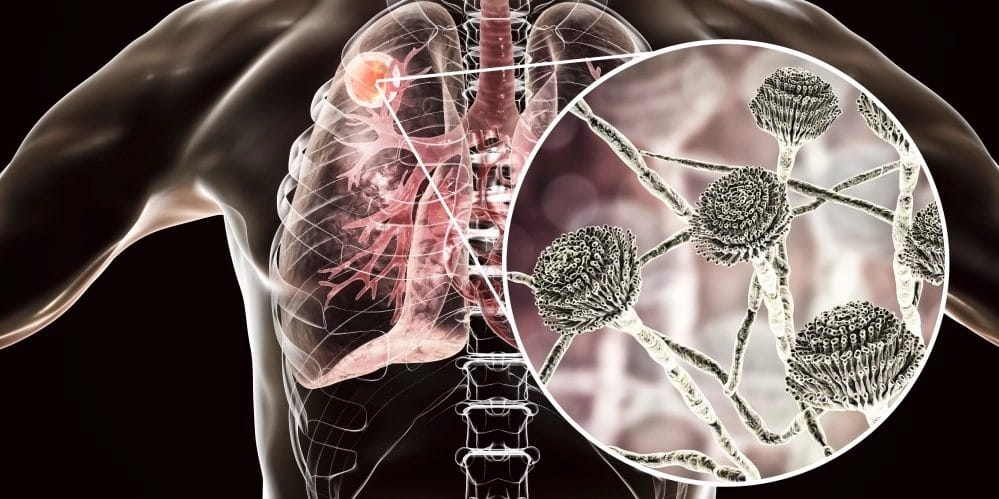

Часто больные интересуются: болят ли легкие при туберкулезе. Несмотря на разъяснение врачей, что легочная ткань не содержит нервных окончаний, люди жалуются, что болит в груди, и связывают появление ощущений с развитием заболевания. Действительно, туберкулезный процесс, может стать причиной болей, но появление симптома связано не с распадом легочной ткани, а с осложнениями течения болезни.

2. Абсцесс легкого

Такое происходит, когда туберкулезная инфильтрация окружена соединительнотканной оболочкой, изолирующий патологический процесс от здоровых тканей.

image

Спровоцировать развитие абсцесса могут:

• распад легочной ткани;

• присоединение вторичных инфекций;

• долгое пребывание в сыром холодном помещении;

• травмы ребер;

• вредные привычки.

Абсцедирование характерно для тяжелого течения туберкулеза, когда у человека истощены иммунные силы.

Основными признаками абсцедирования являются:

• повышение температуры;

• слабость и апатия;

• кровохаркание.

Болезненные ощущения в легких при туберкулезе, осложненном абсцессом, умеренные, основными признаками являются лихорадка и кровохаркание.

Абсцесс легкого при туберкулезном процессе у детей почти не встречается, а вот взрослые часто страдают от этого осложнения.

Больных госпитализируют и назначают противовоспалительную терапию, а также препараты для устранения сопутствующей симптоматики (обезболивающие, жаропонижающие). При благоприятном течении болезни гнойник самостоятельно вскрывается, и содержимое откашливается с мокротой. Стенки опустевшей капсулы смыкаются и срастаются между собой. После заживления остается рубец.

Когда очаг расположен в нижних отделах легкого или симптомы заболевания не устраняются медикаментозными средствами, показано хирургическое вмешательство, когда иссекается доля легкого вместе с абсцедированным участком. После операции проводится курс антибиотикотерапии.

При появлении боли, кровохаркания и лихорадки нужна консультация фтизиатра. При выявлении абсцесса больные госпитализируются в противотуберкулезный стационар.